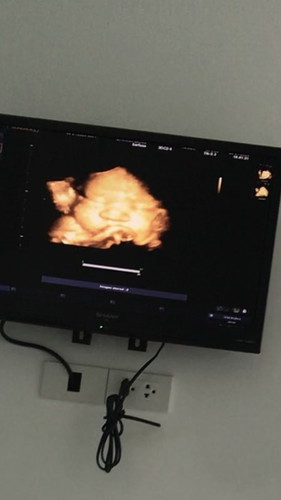

37+1 น้ำหนักลูกน้อย

เมื่อวานไปหาหมออยากรู้ลูกเป็นไงบ้างฝากกับ ร.พรัฐ หมอไม่ซาวให้เลยไม่รู้น้ำหนักไม่รู้อะไรเลย เลยเลือกไปคลีนิกให้หมอซาวให้หมอบอกน้ำหนัก1990น้ำหนักน้องน้อยมาก ต้องทำไงให้น้ำหนักน้องเพิ่มขึ้นคะเครียดมาก🥺##ขอบคุณสำหรับคำตอบค่ะ #ขอคำแนะนำหน่อยค่ะ #คุณแม่ๆช่วยแนะนำหน่อยค่ะ

บ้านนี้37น้ำหนัก1990กังวลมาก😢

ในรูปจํ่ามากเลยค่ะเเม่ เเม่ฟังผิดรึป่าวคะ ใกล้คลอดขนาดนี้ ต้อง2อัพเเล้วนะเเม่ เเต่ไม่เป็นอ่ะไรค่ะ น้องออกมาโตข้างนอกได้งับ🥰